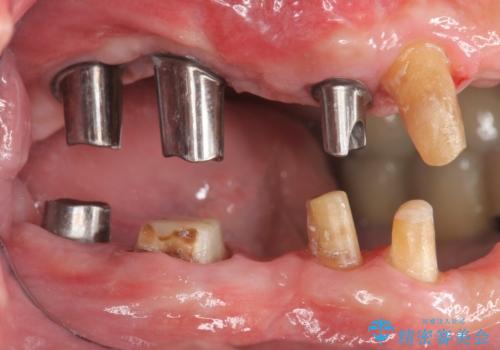

歯の根本まで骨吸収が進み、ぐらぐらになってしまった歯を抜去し骨の造成を行ったのちインプラント治療を計画します。

重度に吸収してしまった歯槽骨をしっかりと造成を行ったのちにインプラント治療を行ったので、安定した歯周環境にすることができました。